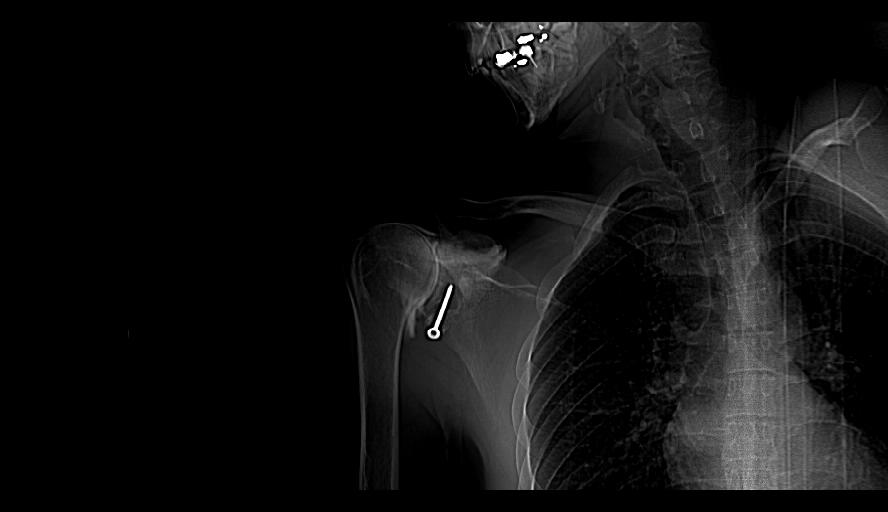

J’ ai dû me faire opérer, oh pas de grand chose, une luxation d’ épaule mais le chirurgien s’ est complètement planté, j’ étais dans un sale état quand enfin j’ ai rencontré un médecin disposé à m’ aider, on me l’ avait bien caché, il a cependant dû me réopérer trois fois.

Les hôpitaux publics me redirigeaient toujours vers l’ établissement qui m’ a raté, le service concerné prétendait que tout allait bien, que la greffe n’ avait pas prise mais qu’ elle ne bougeait pas ( examen réalisé au papier calque). Je repartais avec des ordonnances contre la douleur de plus en plus gonflées, un jour on m’ a demandé si c’ était pour un cheval lorsque j’ ai voulu reproduire l’ une d’ elles.

J’ ai tenté de porter plainte contre l’ hôpital, il parait que ça ne se fait pas, ça m’ a coûté des nerfs et pas mal d’ argent pour des rapports qui informent que la greffe était mal positionné, qu’ elle ne pouvait pas prendre mais que l’ on ne peut cependant pas considérer qu’ il s’ agit d’ une erreur. De quoi s’ agit t’ il alors ? D’ une expérience ? Est ce que j’ ai servi de cobaye ? Je n’ en saurai jamais plus, le dernier expert m’ a conseillé d’ abandonner, que j’ allais me noyer dans cette affaire.